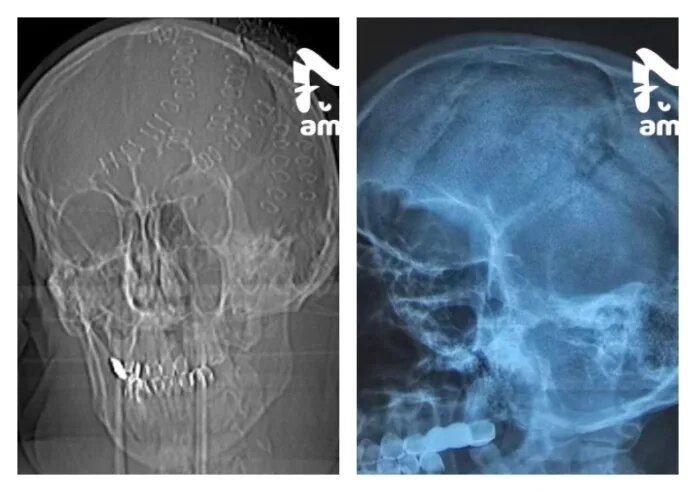

Врачи Владивостока спасли жизнь 50-летнему жителю Приморья, которому раздробили череп ударом топора.

Мужчину с острова Попова доставили в больницу с тяжелейшими травмами головы — множественные вдавленные переломы темени, ушиб мозга, обширное кровоизлияние и резаные раны. Он находился в шоковом состоянии. Об этом пишет тг-канал Amur Mash.

Хирурги экстренно провели многочасовую операцию, во время которой удалили фрагменты разрушенного черепа. Пациента удалось стабилизировать.

Сейчас его состояние оценивается как удовлетворительное, он остаётся под наблюдением врачей.